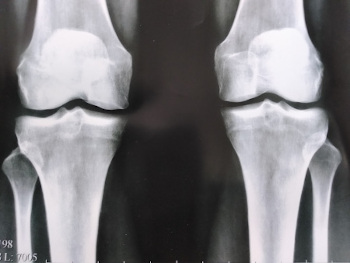

După curs am mers la același specialist. A fost confuz și uimit de ceea ce a văzut.... Mi-a spus că sunt complet sănătoasă și m-a întrebat cum mi-am învins artrita. I-am spus despre gelul Hondro Sol, și este ieftin în comparație cu câți bani am cheltuit pentru remedii pe care mi l-ați dat!